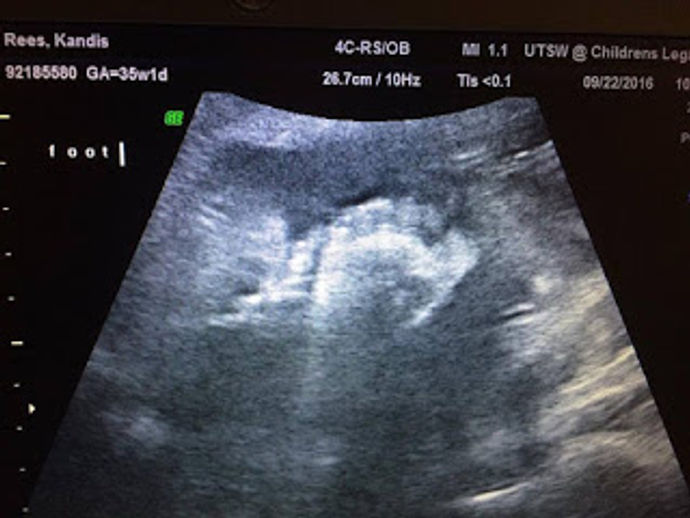

Day 71 of bed rest. This post has me so incredibly emotional. Its so hard to believe that I just completed my last full week of bed rest....

Day 65 of bed rest! That's a total of 9 weeks and 2 days of sitting on my big pregnant butt. haha I've been in the hospital for 7 weeks...

6 weeks down and only 19 days to go until Baby Raylon enters this crazy world. Thankfully this week flew by. I think knowing that the day...

Day 51 of bed rest. I can't believe I just finished my 5th week in this hospital. This week was full of lots of different emotions....

Day 42 of bed rest. It has been a long month and a half. Now I sit here counting down the days until I am 36 weeks pregnant. Only 26...